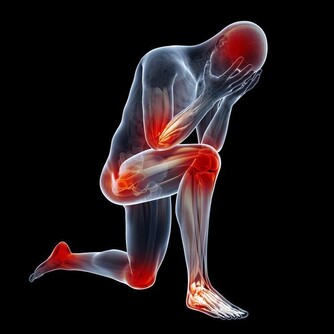

現在很多病,源自缺乏“緩”。比如:神經衰弱、焦慮症、躁鬱綜合徵等,都是這個時代常見的。其實是大家陷入了一種太快、太急的精神心理生活狀態。太急了,神就飄在外面,氣機也浮動不定,既緊且亂,生理功能也就跟著失調了。